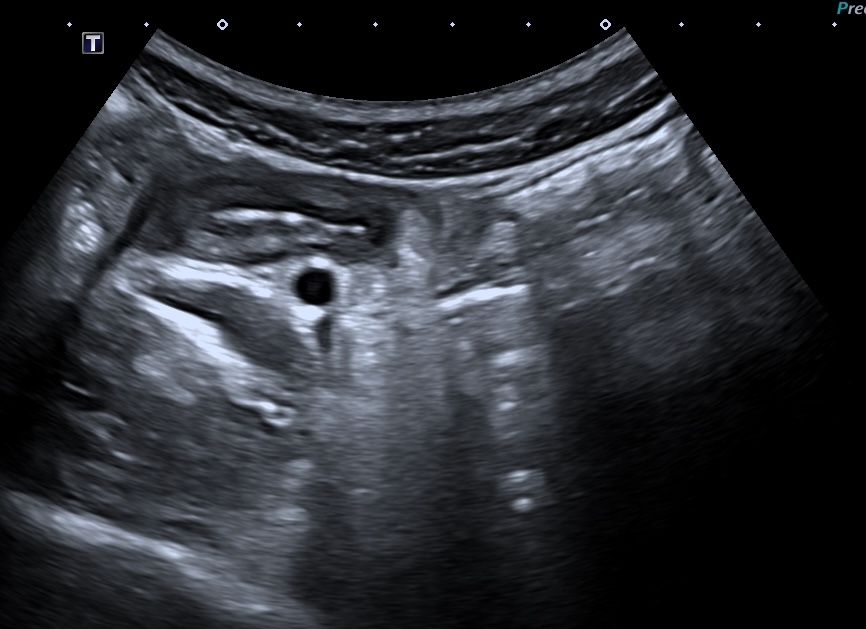

ci-dessous même iléîte terminale vue en basse fréquence et en haute fréquence, iléïte passant devant les vaisseaux iliaques

la sonde HF est la seule qui permette une analyse précise de la paroi